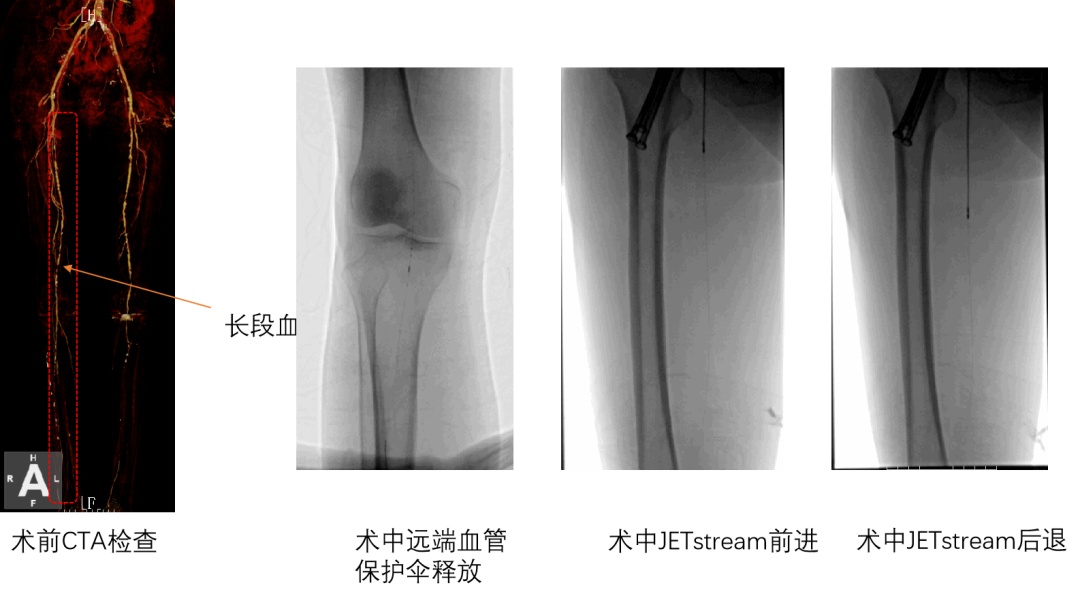

患者李先生(化名)右下肢足趾反复溃疡逾一年,虽经多次伤口护理及换药治疗仍难以愈合。术前评估显示其病情危重:下肢动脉ABI检测提示严重缺血,下肢动脉CTA检查明确右下肢股浅动脉多发节段性狭窄闭塞,膝下动脉胫前及胫后动脉闭塞。

面对下肢动脉多发节段狭窄病变,在上海交通大学医学院附属第九人民医院血管外科专家指导下,区中心医院血管外科团队经详细评估,首次采用国际先进的JETSTREAM血管斑块旋切系统进行微创介入治疗。手术中,团队通过血管造影精准定位病变部位,利用JETSTREAM的高速旋切功能清除血管内斑块,成功开通闭塞血管,恢复血流。这套“血管清道夫”系统配合低剂量药物涂层球囊扩张技术,既彻底清除了顽固斑块,又有效抑制了血管再狭窄风险。